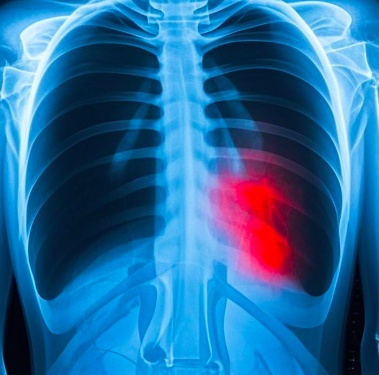

王先生最近参加了社区组织的老年人年度体检,因胸片体检结果异常疑似肺结核,社区卫生服务中心医生在电话里督促王先生到区结核病定点医疗机构进一步就诊。他心里直犯嘀咕,家附近的三甲医院不是更好么?医生为什么要叫我到结核病的定点医疗机构就诊呢?

疑似肺结核,为什么必须到结核病定点医疗机构诊治?

肺结核是我国重点防控的慢性呼吸道传染病,原卫生部颁布的《结核病防治管理办法》中明确规定:结核病定点医疗机构负责肺结核患者的诊断、治疗并落实治疗期间的随访检查。非结核病定点医疗机构接诊结核病患者和疑似患者后,应将其转诊至定点医疗机构。我国省、地、县三级均设有结核病定点医疗结构,结核病门诊和病房的设置均符合《医疗机构管理条例》规定和呼吸道传染病诊疗及防护要求。